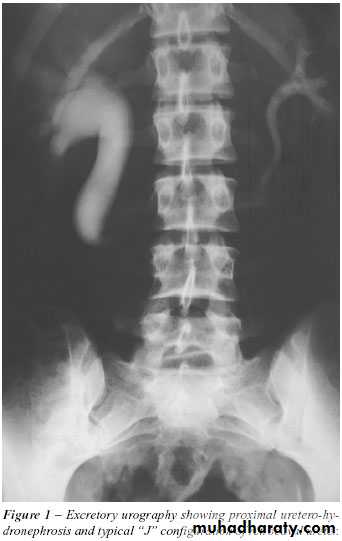

Infantile hydronephrosis ( PUJ OBSTRUCTION ):

IVU shows :

Marked dilatation of pelvis and may be extra-renal.

Calyceal dilatation is late and in advanced cases form foot shape PCS

The ureter is not seen and when it is seen looksnormal .

Delayed film with I.V. diuretic produce gross dilatation .